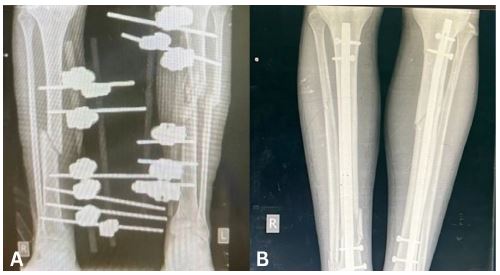

An 18-year-old male presented with fractures sustained during a bombing. He had been found under the rubble of a collapsed house after the incident. He sustained a Gustilo-Anderson Grade II open fracture of the proximal tibia on the left and a closed fracture of distal tibia on the right. There was also a fibular fracture on the left. At the time of his first presentation, soft tissue was repaired and external fixators were used to stabilise the fractures on both sides. These were in place for 14 weeks during which the patient was non-weight bearing and completely bed-bound. After 14 weeks, there was no sign of bone healing on radiography (Figure 5A). Plans were made for external fixators to be removed. Due to a lack of resources and time constraints, external fixators needed to be removed and IMN fixation inserted immediately afterwards during the same session (Figure 5B). To prepare for this, he was started on a regimen of IV Ceftriaxone 48 hours prior to the removal of the external fixators. The patient began weight-bearing as tolerated 2 days after intramedullary nailing. Wounds were found to have healed two weeks after intramedullary nailing, a total of 16 weeks after his initial presentation.

Figure 5: (A) Anteroposterior view radiograph of both legs showing external fixators in situ. (B) Anteroposterior view radiograph of both legs showing intramedullary nails in situ.